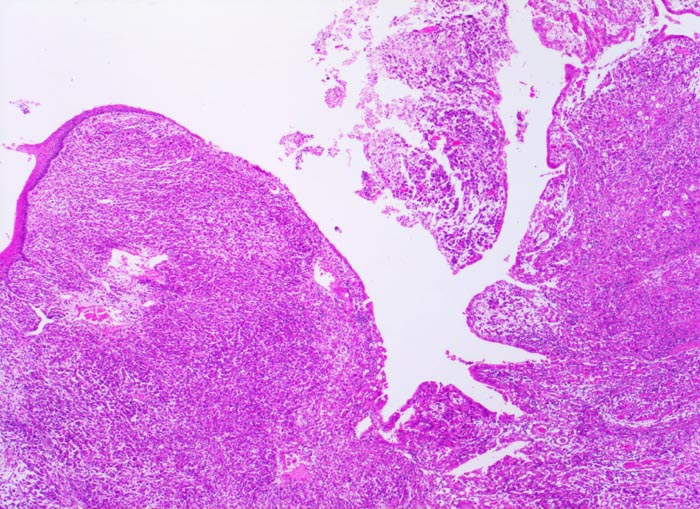

Magenkarzinom: Tumorinfiltration des Ösophagus

Das Karzinom breitet sich diffus in der Wand von Magen und Ösophagus aus. Die Ösophagusschleimhaut (links im Bild) und das Oberflächenepithel des Magens sind intakt.

Diffuse Verdickung und Versteifung der Magenwand im Sinne einer Linitis plastica bei intakter Schleimhautoberfläche. Aufhebung des Faltenreliefs.

Seit einigen Monaten klagte der Patient über unspezifische Oberbauchbeschwerden.